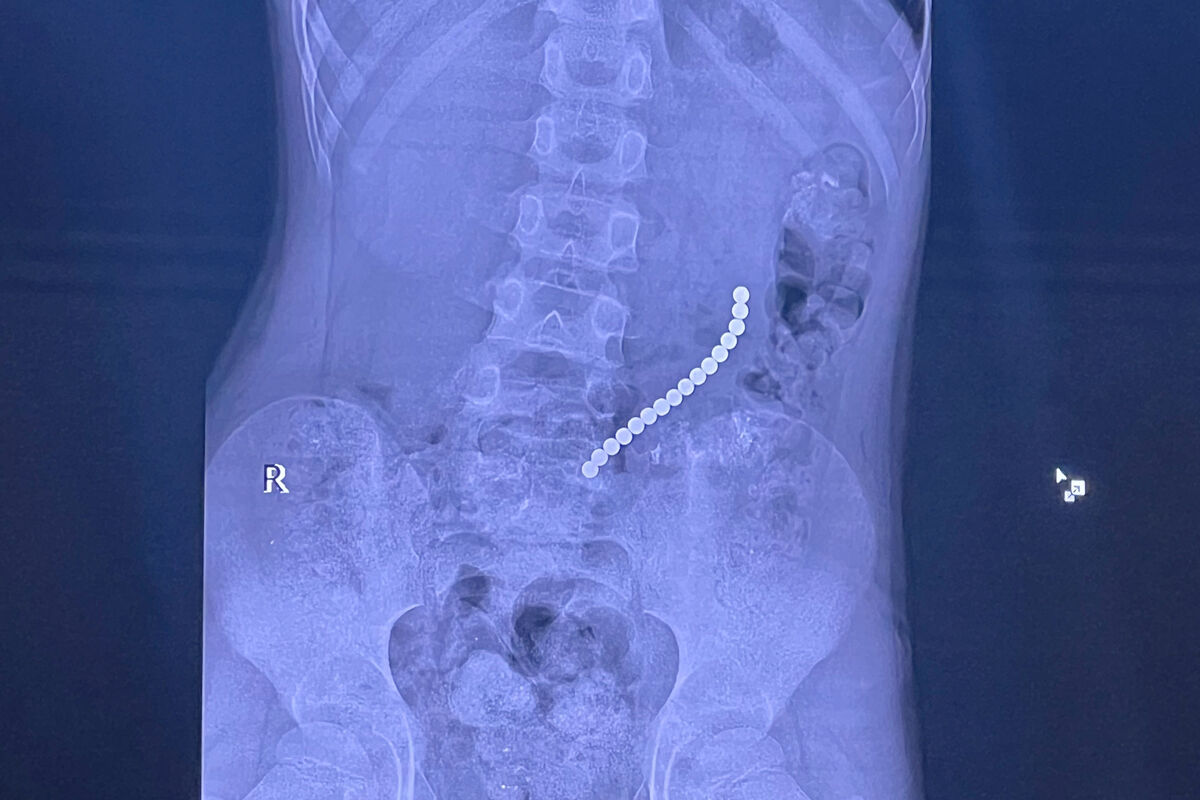

Российский школьник проглотил 16 магнитных шариков

В Иркутске спасли восьмилетнего мальчика с 16 магнитами в желудке и кишечнике

Врачи Иркутской областной детской клинической больницы спасли восьмилетнего пациента, который проглотил магниты. Об этом сообщил главврач больницы, член-корреспондент РАН Юрий Козлов на своей странице во «ВКонтакте».

Медик отметил, что ребенок поступил в медучреждение с жалобами на «острый живот». На обследовании специалисты обнаружили 16 магнитов, которые соединились между собой в различных сегментах внутренних органов.

«Очень редкое сочетание: одни магниты находились в желудке, другие — в начальном отделе тонкой кишки. Это привело к образованию фистулы — сообщению между желудком и кишкой», — поделился Козлов.

С помощью технологий минимально-инвазивной хирургии врачи извлекли инородные предметы, разделили органы и восстановили их целостность.